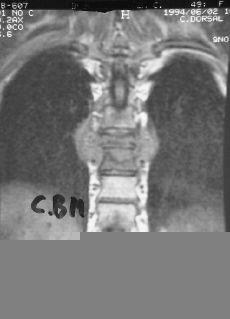

El uso del TAC y la RM ha supuesto un avance fundamental en el estudio de mal de Pott, ya que permiten un conocimiento exacto de la extensión de las lesiones y además conocer la repercusión del proceso en el canal medular. Aunque la TAC aporta un magnífico estudio de las lesiones óseas (Fig. 7), las ventajas de la RM es que, además de una mayor precisión, aporta una mejor imagen topográfica y permite conocer las posibles alteraciones meníngeas o medulares, así como las repercusiones del proceso en el canal medular22 (Fig. 8). Actualmente la incorporación de la TAC de tipo helicoidal ha mejorado los estudios clásicos anteriores.

Figura 8. Imagen de RM con absceso intrarraquídeo.

Nuestra experiencia, coincidente con la de otros autores,4,20,22 indica que hay un menor número de cuerpos afectos en la osteomielitis vertebral. En T1 la intensidad es más homogénea en la osteomielitis que en las lesiones tuberculosas, y con respecto al estudio de los abscesos tras la administración de gadolinio en los de origen tuberculoso el reforzamiento de los bordes es mucho mayor que los de etiología inespecífica.